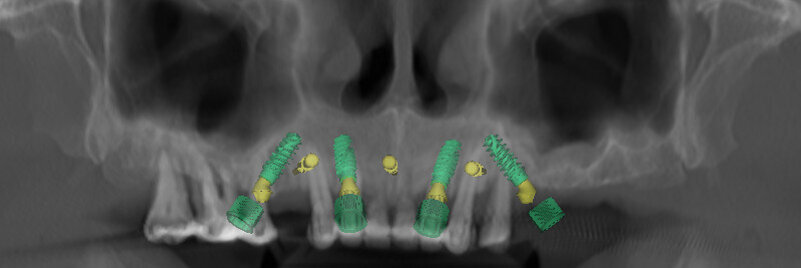

An intra-oral scan was taken to record the patient’s current oral situation, and the resulting STL file and the DSD fil (2D smile design image) were used to create the future prosthetic design with software for the laboratory (Figs. 3–6). The 3D radiographic DICOM data and the prosthetic design project STL file were superimposed in coDiagnostiX (Figs. 7–9) The fixation pin guide, bone reduction guide, surgical guide and bite registration guide were designed with coDiagnostiX (Figs. 10–13) and produced using 3D printing technology.

To design the prosthesis digitally, we first selected the screw-retained abutment (SRA) angle and gingival height (Fig. 14) and then we created the patient model on which we could connect the BLX implants with the SRAs selected from the Straumann library (Fig. 15). The implant placement guide was on the model, leveraging the high stability that we could gain from palatal support (Figs. 16 & 17). After printing the model, the BL  implant analogues were positioned using the template for navigation. The digital planning using coDiagnostiX (Version 9.14) allowed the dental technician to identify all the necessary parameters related to implant position (Figs. 18–22). Emergence profiles were set-up on the model (Fig. 23). The model was scanned using scan bodies, and a CAD/CAM temporary restoration was designed and milled in a PMMA-based restorative material (Figs. 24–29).

On the day of surgery, we prepared for the surgical protocol provided by the implant planning software, which guided us on the drilling sequence and the use of the appropriate instruments for the implant bed preparation (Figs. 30a & b). After the fixation pins had been allocated, teeth #17, 16, 15, 13, 12, 22, 23 and 24 were atraumatically extracted and alveolectomy was performed using a bone reduction guide (Figs. 31–36). Four implants (Straumann BLX; regular base; diameter: 4.5 mm; length: 12.0 mm) were placed, two straight implants in the anterior and two titled implants in the posterior. All the implants were stabilised to a torque of 50 Ncm (Figs. 37–43), and the SRAs were placed on top. The SRAs on the posterior implants had an angulation of 30° (diameter: 4.6 mm; gingival height: 3.5 mm) and on the anterior implants an angulation of 17° (diameter: 4.6 mm; gingival height: 3.5 mm; Figs. 44 & 45).